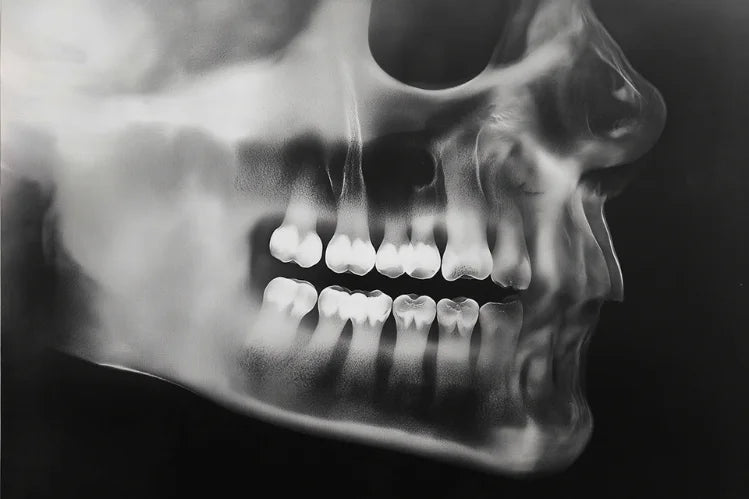

Les dents postérieures désignent les dents et les tissus situés à l’arrière de la bouche, en particulier les molaires et les prémolaires. Les gens ne voient généralement pas les dents au fond de votre bouche lorsque vous souriez. Cependant, cela ne signifie pas qu'ils sont moins importants à entretenir.

Les prémolaires sont situées entre les canines et les molaires. Les adultes ont généralement 8 prémolaires, 4 sur la mâchoire supérieure et 4 sur la mâchoire inférieure. mâchoire inférieure.

Les molaires sont situées tout au fond de la bouche, sur les mâchoires supérieure et inférieure. Les adultes ont généralement 12 molaires, trois de chaque côté des mâchoires supérieure et inférieure, y compris les dents de sagesse. Cependant, certains adultes ont moins de molaires en raison d'extractions ou de dents de sagesse congénitalement absentes.

Anatomie des dents postérieures

Cuspides

En dentisterie, une cuspide fait référence à la projection pointue ou arrondie, trouvée sur les surfaces de mastication des molaires et prémolaires.

Fissures et rainures

Les fissures et les sillons sont des creux et des lignes profondes sur la surface occlusale qui favorisent la décomposition des aliments mais retiennent également la plaque dentaire.

Émail

L'émail est la substance la plus dure du corps, qui protège la dent de l'usure et de la carie.

Dentine

La dentine se trouve sous l’émail et transmet des signaux sensoriels à la pulpe.

Racines

Les racines offrent un ancrage solide pour les forces de mastication importantes.

Pulpe

La pulpe contient des nerfs et des vaisseaux sanguins, fournissant des nutriments et des sensations à la dent.